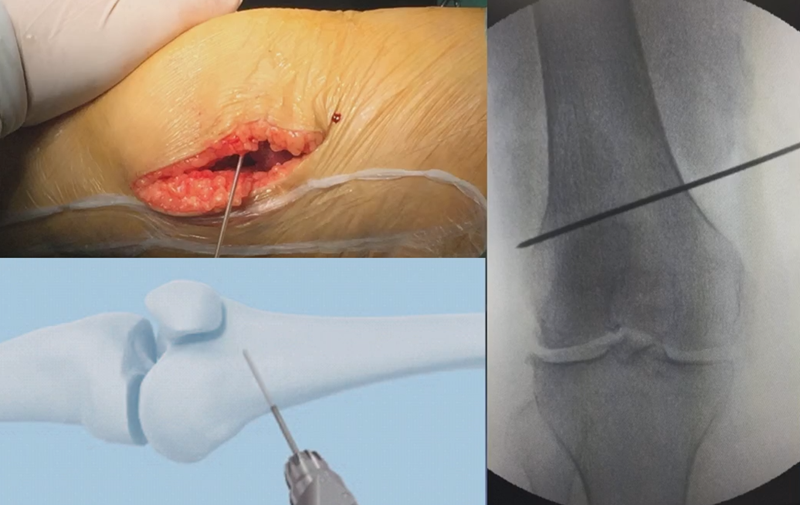

4、截骨

合页点和截骨线已确定好,按照术前计划打入导针,测量截骨深度。

注意,目前临床推荐的DFO要求最好能做双平面截骨,即还要有一条上行截骨线,上行截骨线与水平截骨线夹角大概为95° 左右。这种截骨方式一方面可以增加稳定性,同时也可以减少对上方髌股关节的干扰。

上行截骨时,要保持肢体旋转中立位,前方要有骨撬保护,由内向外完全截开,上行截骨线不存在合页。

水平截骨时,同样放肢体中立位,后侧放一把骨撬保护后方重要结构。

截骨过程中,不要求一次截骨到位,把合页深度全部截到,可以留最后一点,用钻头由前向后打出一排筛孔来,把合页端弱化,再去做闭合时就不容易折断了。